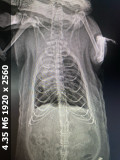

Вот снимок рентгена, сейчас дышит более менее хорошо, но видно что бока ходят. Ест хорошо, но заметил что спит внизу клетки а не сверху в гамаке как обычно было до смерти его друга Омлетушки (ОГМ)